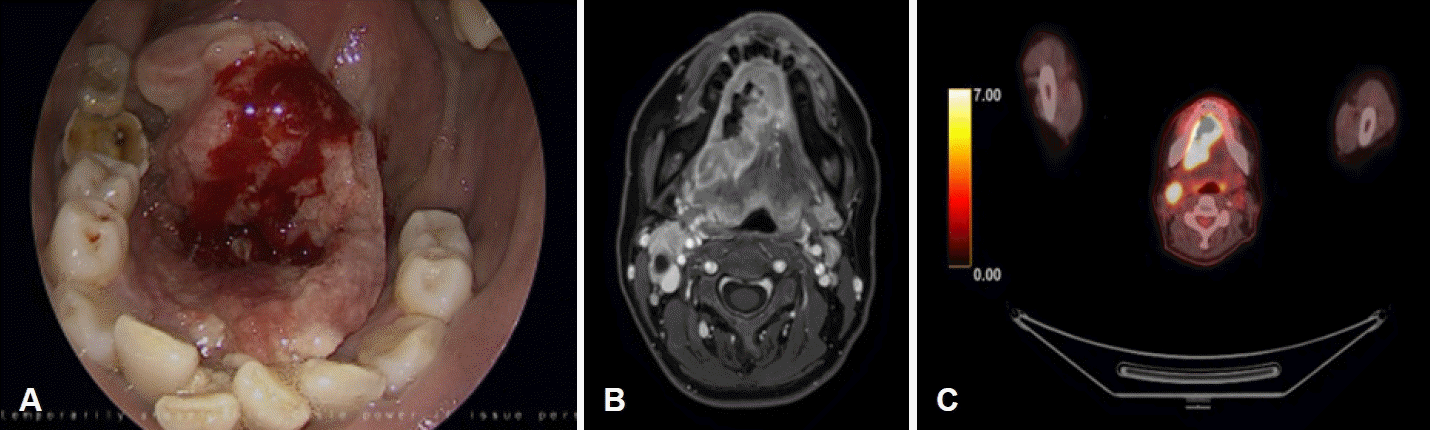

A 45-year-old female with a history of smoking initially presented with painful ulcerative mass at right mouth floor that started 3 months ago (Fig. 1A). This patient was diagnosed with squamous cell carcinoma of mouth floor right (cT4aN2cM0) by punch biopsy and imaging work up. Neck CT and MRI showed a huge irregular mass in the mouth floor and anterior tongue areas. And no distant metastasis was found on PET-CT (Fig. 1B and C). This patient was especially suspected of invading the mandible cortex by MRI and dental scan imaging. We decided to perform a wide excision of mouth floor and anterior tongue with subtotal mandibulectomy, modified radical neck dissection bilateral, tracheostomy and reconstruction with fibular free flap with VSP. Written informed consent was obtained from this patient before surgery. This study was approved by the Institutional Review Board of Yongin Severance Hospital.